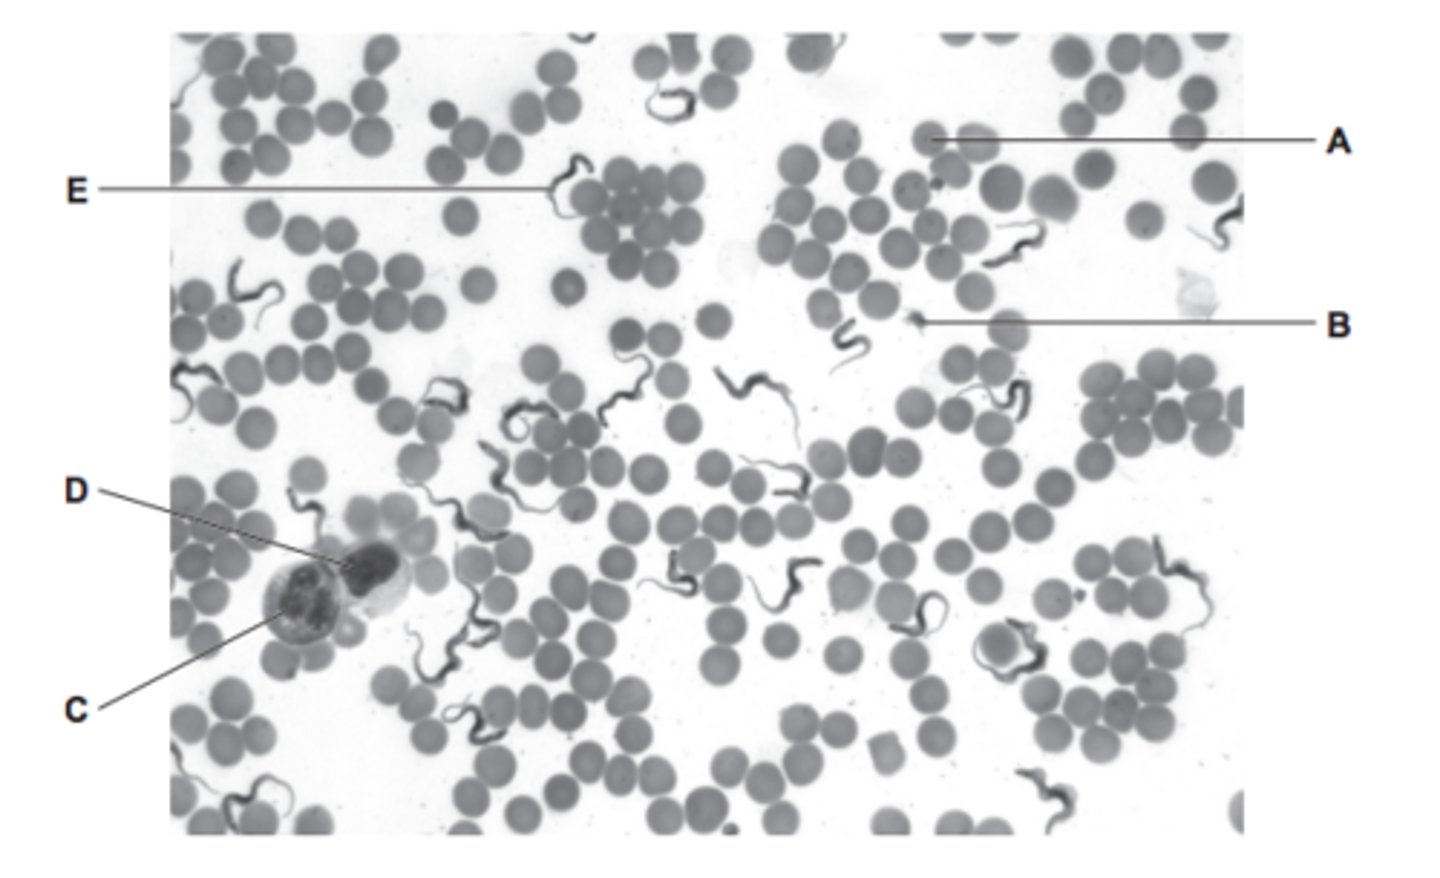

blood smear

identify A and B

lighter colour cells = erythrocytes

darker colour cells = neutrophils

name A - E

A - erythrocyte

B - platelet

C - neutrophil (lobed nucleus)

D - lymphocyte (large nucleus, takes up most of cell)

E - protist

how do you distinguish between a monocyte and lymphocyte under a microscope?

monocyte has a kidney bean nucleus, lymphocyte have a large nucleus that takes up most the cell